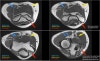

* Ulnar neuritis

There is enlargement of the nerve. On the T2W-image there is high signal.

Another sign is non-uniform enlargement of the fascicles, which is seen on the sagittal image (arrow).